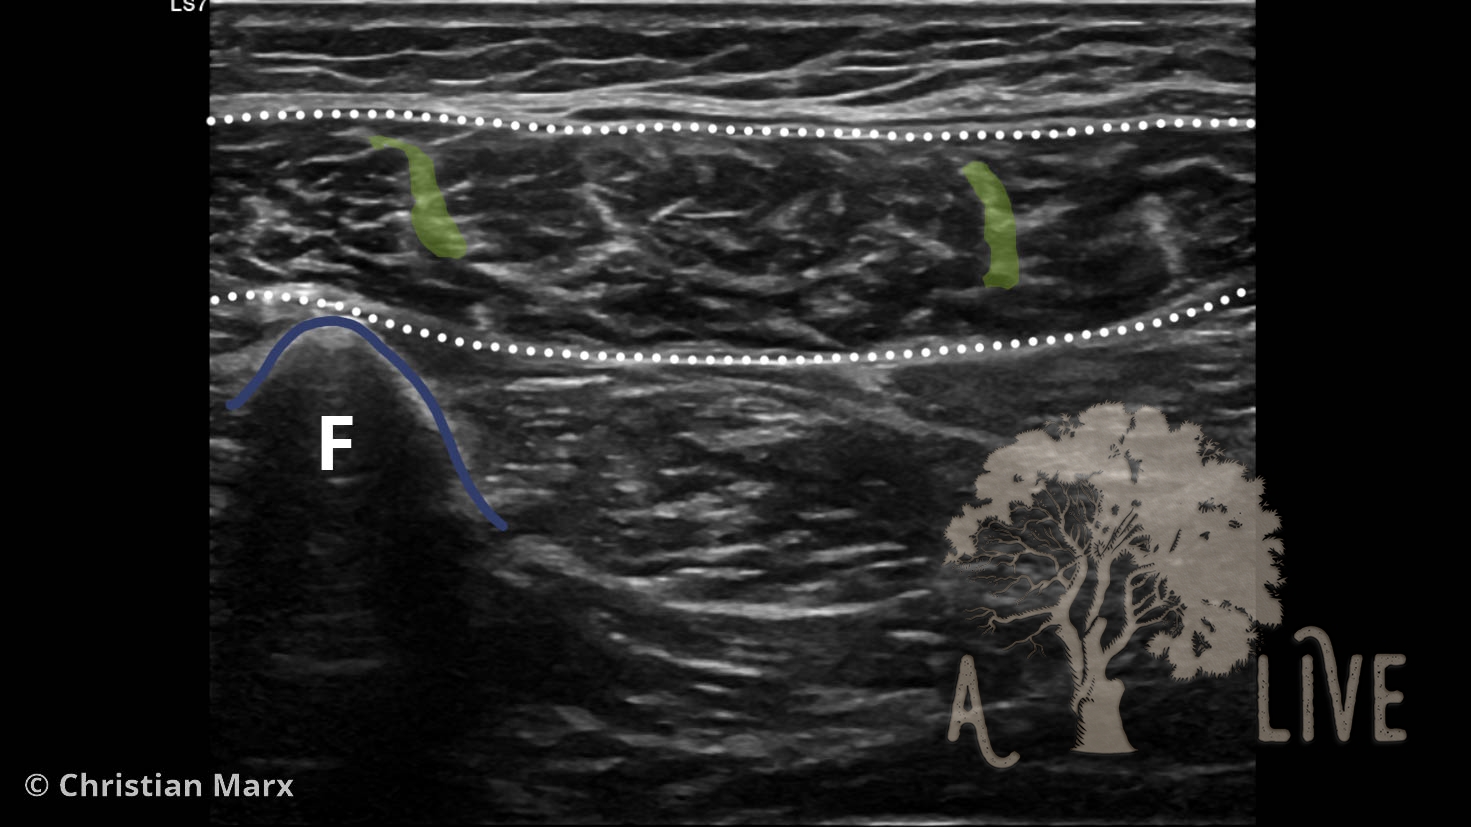

muscle the rheumatologists view